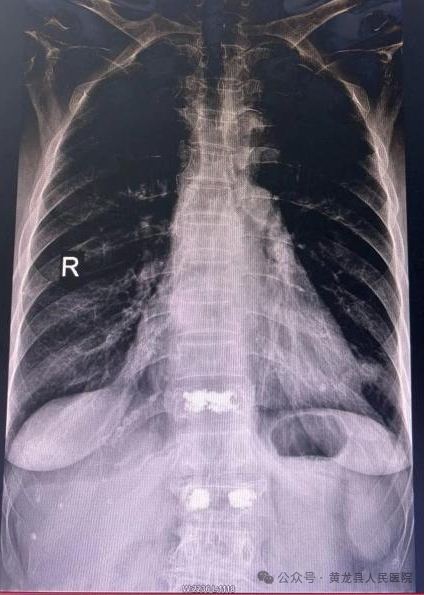

患者女,88岁,因病理性骨质疏松导致胸腰背部疼痛,翻身、弯腰、下地活动严重受限。入院后行X线检查示:胸椎体压缩性骨折(胸11)。

术前术后X线影像

术中最大限度保留了腰背肌肉的完整性,减少患者术后疼痛、手术出血和切口感染等手术并发症,同时大大缩短了患者康复时间。术后第1天,患者胸腰部疼痛显著缓解,不仅能自行完成床上翻身活动还可以下地活动,达到预期效果,术后第2天出院,恢复生活自理能力。患者及家属对手术治疗效果非常满意,向方继荣主任及外科全体医护人员多次表示感谢,出院后特送来锦旗一面再次表示感谢。